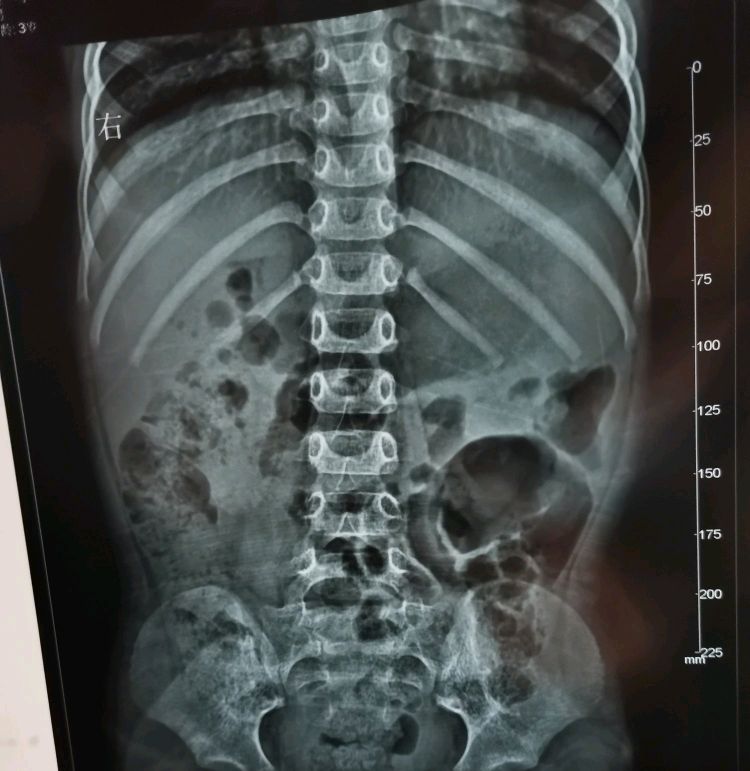

当时心急如焚,赶紧又去找医生检查,医生看后就问都吃过什么东西,在什么地方玩过,孩子也没吃别的东西啊,就是在家正常吃饭后自己在那玩,后来说肚子疼就跑来医院检查,谁知道现在突然起了这么多疙瘩,医生说疙瘩是散布的,白色的片状,初步诊断是过敏性*麻疹荨**,应该是吃了什么海鲜之类的或对什么过敏导致的,当时考虑有点严重,医生赶紧给打了针抗过敏药,对于一个三岁小孩来说,屁股上第一次打针真的是哭的黑天暗地,撕心裂肺,(心跟猫抓一样[流泪],虽然我是一名男儿身的父亲)因为孩子肚子也不舒服,然后就继续去排队做检查,拍片子,即使打了抗过敏针,拍片子的时候儿子还是身上痒,动来动去,试了几次机器都无法拍照,当然最后按着儿子的头,手和脚给做完了检查,结果出来看片子,医生说肚子里有一大团胀气,

别的没啥问题,应该是快过年了吃肉消化不良导致,以后一定注意了,孩子小,肠胃什么都没发育完好。不要吃太多不易消化的食物,否则受罪的都是孩子,后来想想真是的,有时候不能对孩子太溺爱了,回到家后吃了医生开的促进消化的药,搂着儿子在床上看动画片,好缓解儿子的疼痛,但过了十几分钟疙瘩还没下,儿子还是老说痒,就赶紧问医生什么情况(看病时加了微信,方便病情询问),医生说再等半小时看看,后来疙瘩慢慢消失了,到晚上10点的时候孩子突然又叫痒,一看又起了一身疙瘩,见状赶紧又带儿子去了更大一点的人民医院检查,到那医生一看还说是过敏*麻疹荨**,说比较严重,赶紧给开了涂抹的药和吃的药